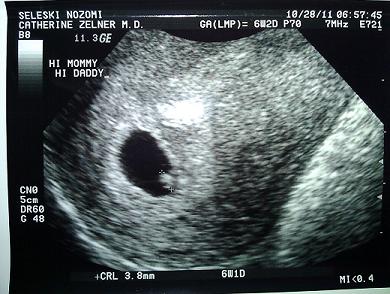

心拍確認されたときのエコー。